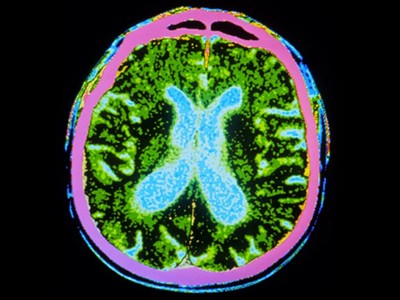

圖1:帕金森病的干細胞療法。

帕金森病是由于大腦中釋放多巴胺(多巴胺能)神經元逐漸喪失所致。Sawamoto 等人1和 Tabar 等人2進行了一項基于干細胞治療的臨床試驗。兩個團隊都使用了臨床級多能干細胞來補充多巴胺能神經元,這種細胞可以無限分裂并分化為任何細胞類型。Sawamoto等人使用了源自健康成年捐贈者細胞的誘導多能干細胞系,而Tabar等人使用了源自早期胚胎的人類胚胎干細胞系。干細胞經過培養,形成多巴胺能神經元祖細胞。這些細胞被移植到稱為殼核的大腦區域,殼核與尾狀核一起形成紋狀體。紋狀體與黑質相連,而黑質是多巴胺能神經元損失最為嚴重的部位。早期(I/II期)臨床試驗主要證實了該療法的安全性,同時也表明其在改善癥狀方面具有一定有效性。